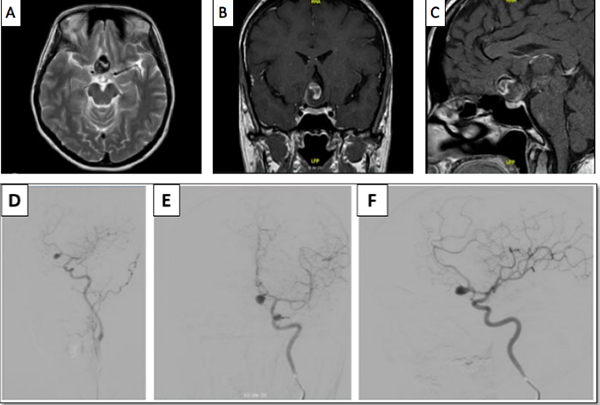

Paciente de género femenino, de 51 años de edad, que consultó a oftalmología por un cuadro clínico de 20 días de evolución consistente en disminución súbita de la agudeza visual del ojo derecho, no asociado a dolor, síntomas sistémicos, ni compromiso de los movimientos oculares. En la evaluación  inicial se encontró en el ojo derecho un defecto pupilar aferente, agudeza visual mejor corregida de 20/400, discromatopsia con test de Ishihara 0/14,  y excavación del 20% en el borde del disco óptico, compatibles con neuritis óptica retrobulbar. En la campimetría por confrontación, se encontró una hemianopsia temporal derecha. A su ingreso a urgencias se le realizó tomografía de cráneo en la que se encontró lesión selar y supraselar, por lo cual se solicitó RMN cerebral contrastada bajo la sospecha de un macroadenoma hipofisiario. En la RMN (Ver Imagen 1) se identificó lesión ovalada, de localización supraselar, con efecto de masa sobre el quiasma óptico y la porción cisternal de ambos nervios ópticos, principalmente del lado derecho, con cambios en secuencias de susceptibilidad, compatible con aneurisma de la AComA parcialmente trombosado.

Figura 1

. RMN de cráneo en la que se identifica lesión sacular de localización supraselar con efecto de masa, mide 22 mm x 19 mm x 17 mm (A), desplaza y comprime el quiasma óptico y la porción cisternal de ambos nervios ópticos, especialmente el del lado derecho (B), tiene un área en forma de media luna que realza tras la administración del medio de contraste (B y C). En la parte inferior se observa la Arteriografía cerebral con un aneurisma sacular de contornos irregulares, localizado en el segmento comunicante anterior de 8mm x 6mm x 5 mm (D, E y F).

Para definir con mayor detalle la anatomía vascular, se realizó una arteriografía (Ver Imagen 1), con la que se confirmó la presencia de un aneurisma sacular de la arteria comunicante anterior, de contornos irregulares, de 8x6x5 mm, sin signos de ruptura con una orientación antero-inferior. Esta clara diferencia entre el tamaño de la lesión en la RNM y la arteriografía confirma la presencia de un trombo intra-aneurismal.

Figura 3

. Arteriografía de control postoperatoria (A y B), en la que se observa adecuada exclusión de aneurisma cerebral